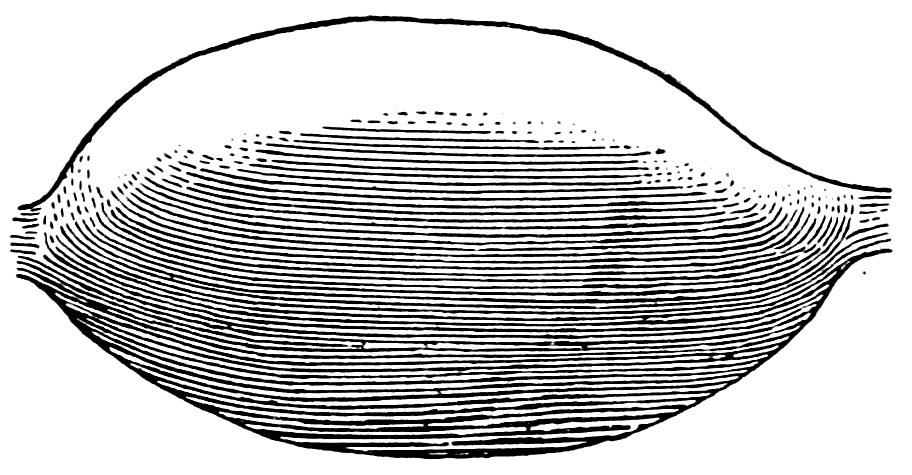

| 15. | Primitive follicles | 58 |

| 16. | Ripening follicles | 61 |

| 17. | Graafian follicles | 62 |